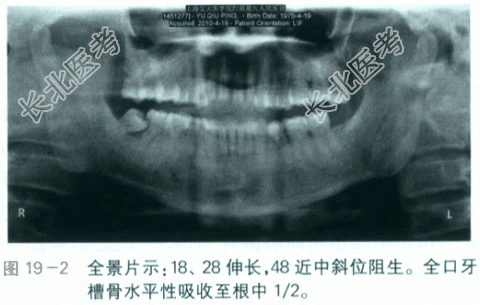

- [材料题] 患者,女性,40岁,近1年来全口牙龈增生,否认有自发痛史。平日有刷牙出血症状,随着牙龈的增生,刷牙出血越来越严重。否认夜磨牙、紧咬牙及口呼吸等不良习惯。既往史:有高血压病史3年余,服用硝苯地平控制良好。否认肝炎、心脏病、糖尿病等疾病;否认其他系统性疾病。否认药物过敏史。否认吸烟及酗酒史。否认有家族遗传史。查体:(1)口外检查:患者面部对称,无畸形,开口度、开口型均正常,未触及肿大的淋巴结。(2)口内检查:牙列完整,18、28伸长,48近中斜位阻生。口腔卫生不佳,牙石Ⅲ°,软垢Ⅲ°,菌斑Ⅲ°。全口牙龈增生明显,覆盖1/3牙面,同时伴有充血水肿,牙龈质地较韧。牙龈增生区域未及明显压痛。全口BOP(+),全口PD普遍5~6mm,AL普遍3~4mm,探及大量龈下牙石,全口牙齿无松动。前牙深覆

(见图19-1)。辅助检查:影像学检查实验室检查(1)血常规检查示:PLT236×10⁹/L,WBC8×10⁹/L。(2)凝血功能:PT11.3s,APTT32.4s。